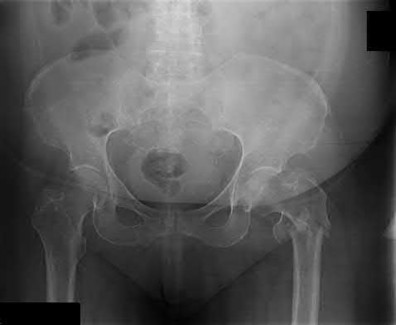

3. # Which of the following is not an appropriate implant for treatment of the fracture seen in Figure A?

The image shows a reverse obliquity intertrochanteric hip fracture.

According to the referenced article by Haidukewych et al, unstable peritrochanteric hip fractures have a worse outcome (failed in 9/16 cases) if treated with a sliding hip screw. Two additional factors that were found to have a strong correlation with postoperative failure (nonunion, loss of reduction) were poor reduction and poor implant placement. In this study, fixed angle devices were superior. Intramedullary fixation has the added advantage of a shorter lever arm and less potential for fracture collapse and limb shortening.

The IMN also acts as a medial buttress.

According to Sanders et al, the dynamic condylar screw (DCS) can also be used in subtrochanteric models, but should not be used if extensive comminution is seen, as they reported a high failure rate with DCS in these fractures if highly comminuted. They report a 77% overall union rate with this device.